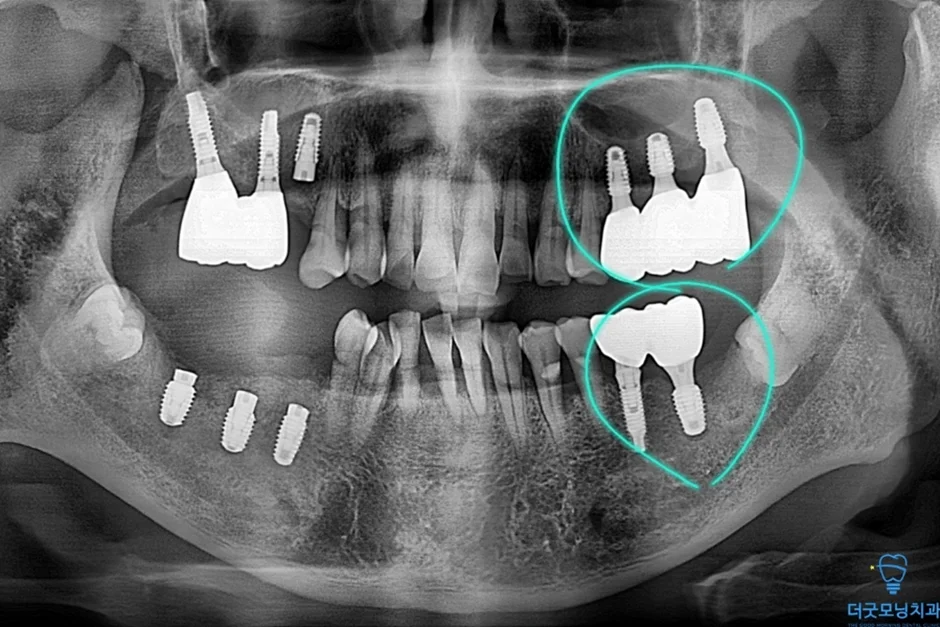

2. 검진 결과 — 파노라마 엑스레이 & CT 분석

먼저 파노라마 엑스레이와 CT를 통해 구강 전체 상태를 확인하였습니다.

아래 임플란트 제거한 사진

임플란트를 치조정 접근 상악동 거상술을 통해 3개의 임플란트가 식립된 사진

하악의 임플란트 주위염 부위는 기존 임플란트를 제거하고 재식립하였으며, 상악의 경우 치조정 접근 상악동 거상술을 통해 3개의 임플란트를 안정적으로 식립하였습니다.